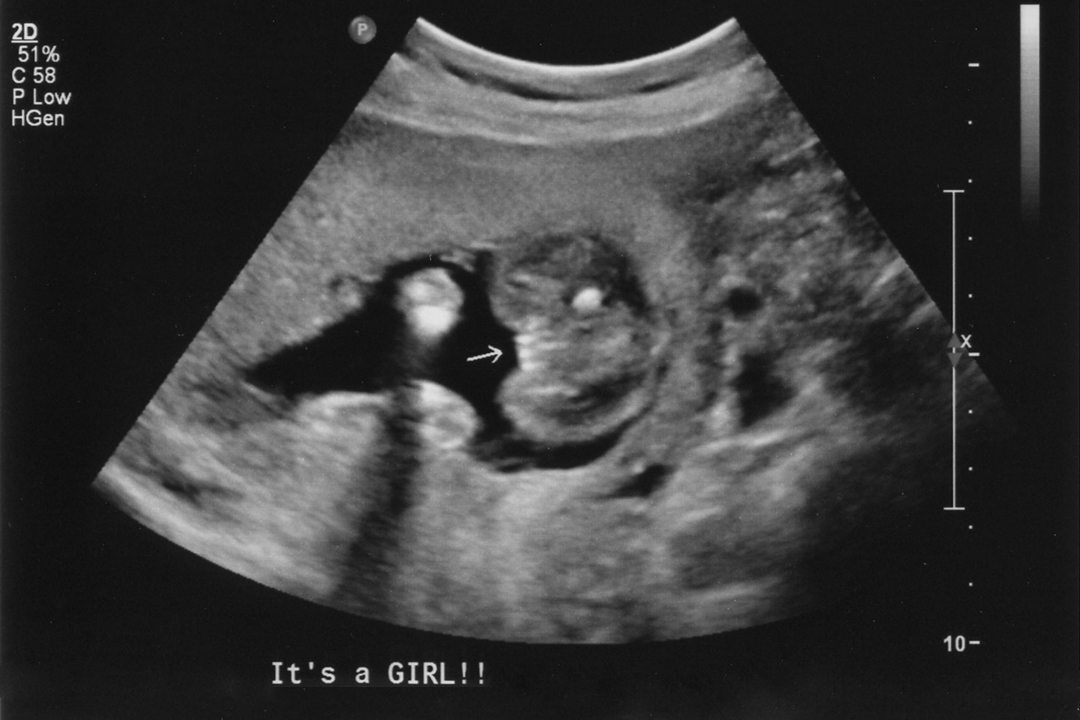

We'll see if I'm uploading these images correctly. :) Top image is from my 20-week scan, the bottom one is at 25 weeks (same hospital, same radiology department, but different ultrasound techs using different machines). I'm 30 weeks now and my doctor did a quick ultrasound today to check baby's position and she, too, confirmed girl.

Attachment 6796